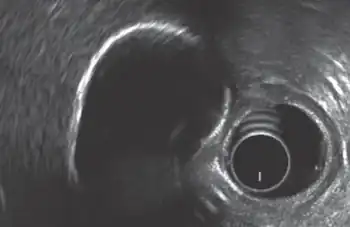

Porcelain gallbladder is a calcification of the gallbladder believed to be brought on by excessive gallstones, although the exact cause is not clear. As with gallstone disease in general, this condition occurs predominantly in overweight female patients of middle age. It is a morphological variant of chronic cholecystitis. Inflammatory scarring of the wall, combined with dystrophic calcification within the wall transforms the gallbladder into a porcelain-like vessel. Removal of the gallbladder (cholecystectomy) is the recommended treatment.

Abdominal radiography (X-ray), abdominal ultrasound or CT scan.